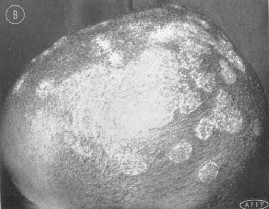

(2)- Vẩy rồng (tinea imbricata, Tokelau): Vi nấm gây bệnh:T. concentricum. Bệnhkéo dàilâu năm nên thường cả mộtvùng da rộng lớn bị, có khi cảthân mình : da không viêm nhưngngứa và tróc vẩy, các vẩy xếpthành hình đồng tâm. Ở Việt nam, bệnh hay gặp ởvùng dân tộc ít người, rất khó chữa.

|

Sang thương vẩy rồng điển hình |